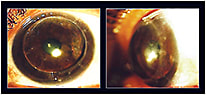

A 46-year-old female underwent a corneal transplant to her left eye to correct a severe post-LASIK ectasia. Postoperatively, the patient had failed with numerous corneal and piggyback lenses and was referred to our clinic for a scleral lens fitting. Optical coherence tomography (OCT) imaging of the patient’s left eye showed significant surface irregularity and a bulge to the graft, with a sagittal height at 15.0mm of 4,300 microns; the average sagittal height of a normal eye at 15.0mm is 3,735 microns. Figure 1 shows the slit lamp appearance at the time of the initial evaluation. Figure 2 shows the axial (power) and the elevation (height) displays of the left eye. In the April 2015 issue, we stated that if the height differential along any given meridian exceeds 350 microns, the patient may be a better candidate for a scleral lens design. In this patient, the height differential was 485 microns.

Figure 1. The patient’s post-surgical bulging graft results in a significant sagittal height—4,300 microns.